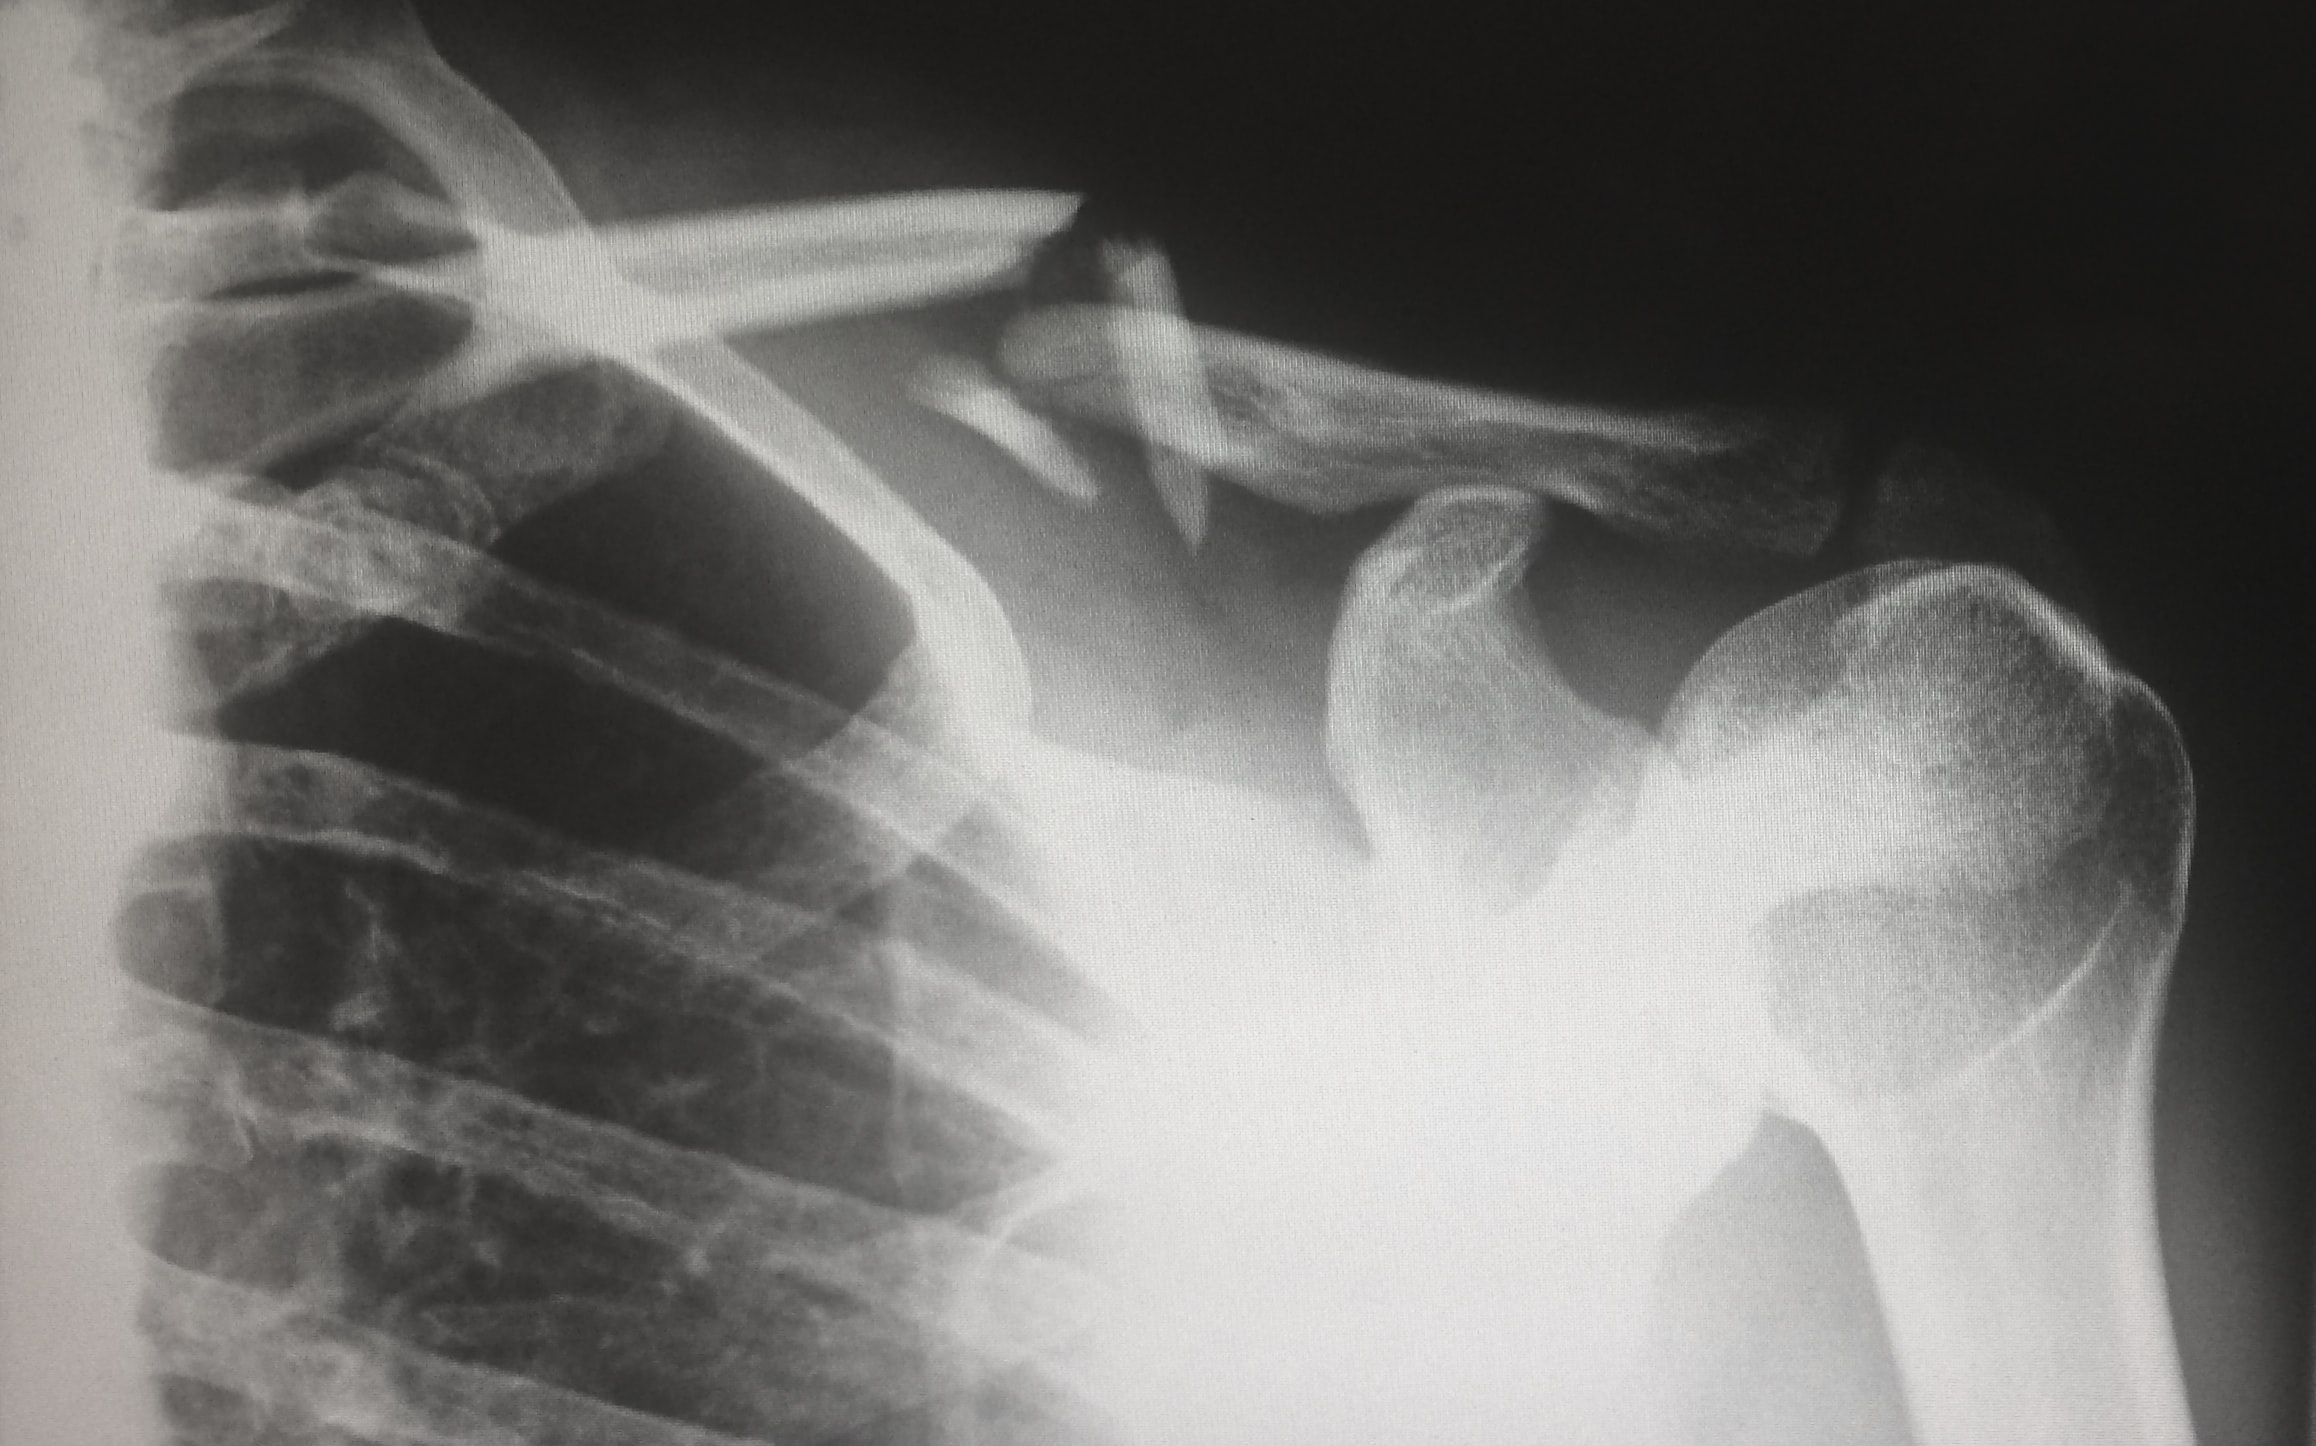

Kompresijas lūzumus visbiežāk izraisa neārstēta osteoporoze. Osteoporozei attīstoties, kauli, tostarp mugurkaula skriemeļi, kļūst trauslāki un vājāki. Ja mugurkaula skriemeļi ir trausli, tie nespēj atbalstīt mugurkaulu ikdienas aktivitāšu veikšanā, un tajos var rasties smalkas plaisas. Plaisām summējoties, mugurkaula skriemeļi var sabrukt, izraisot tā dēvētos kompresijas lūzumus. Cilvēkiem ar osteoporozi pat tik šķietami ikdienišķas aktivitātes kā noliekšanās, lai paceltu iepirkumu maisiņu, spēcīga nošķaudīšanās vai klepošana var izraisīt kompresijas lūzumus.

Vairākiem nelieliem kompresijas lūzumiem summējoties, mugurkauls sāk deformēties. Mugurkauls kļūst vājāks, var mainīties tā forma, un cilvēks kļūst augumā īsāks. Visbiežāk kompresijas lūzumi notiek mugurkaula skriemeļu priekšpusē, jo to veido plānāki kaulaudi. Lūzumiem summējoties, mugurkaula skriemeļi deformējas un ieņem ķīļa formu, veidojot mugurkaulā kuprveida izliekumu jeb kifozi. Tas, savukārt, rada sāpes muguras un kakla rajonā.